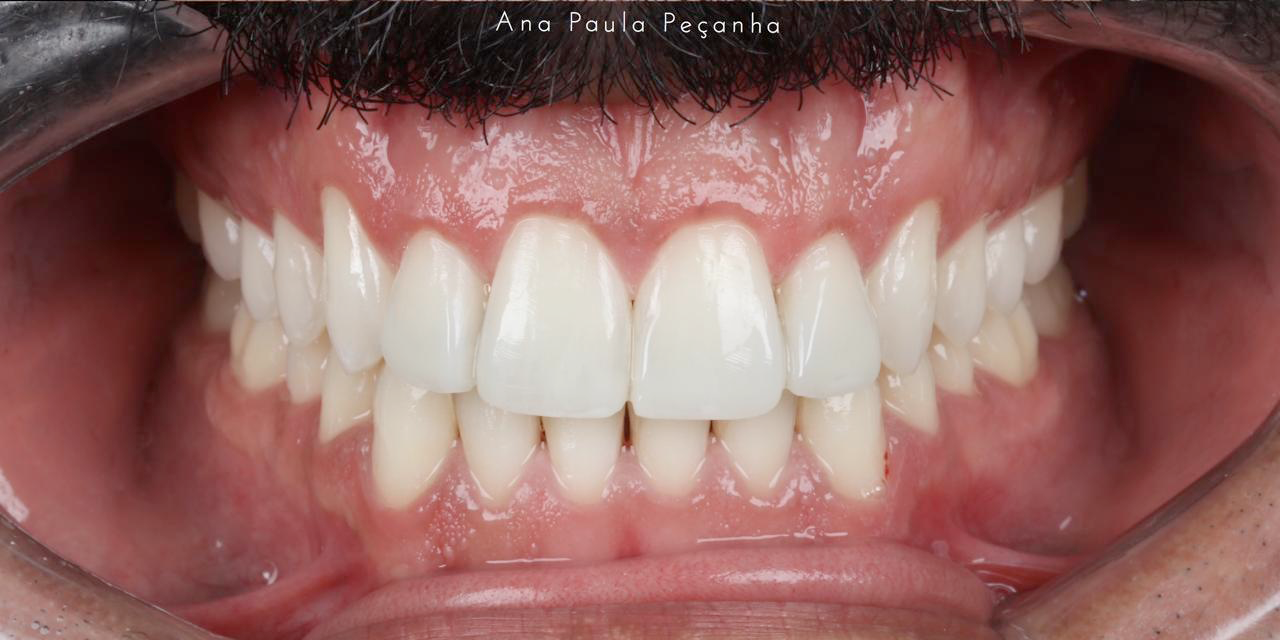

Restaurações Estéticas com Resina Composta: As restaurações estéticas com resina composta são utilizadas para reparar danos nos dentes anteriores (frontais) e posteriores (molares e pré-molares). A resina composta é um material versátil que se assemelha à cor e à translucidez dos dentes naturais, oferecendo uma solução estética e durável. Nos dentes anteriores, as restaurações em resina composta são ideais para corrigir cáries, fraturas, desgastes e manchas, proporcionando um acabamento harmonioso e natural. Nos dentes posteriores, as restaurações com resina composta são utilizadas para reparar cáries e outros danos, garantindo resistência e funcionalidade.

Benefícios da Reabilitação Combinada: A combinação de alinhadores ortodônticos e restaurações estéticas com resina composta permite uma reabilitação completa do sorriso, abordando tanto a correção do alinhamento dos dentes quanto a restauração da sua integridade e aparência. Esta abordagem multidisciplinar assegura que os pacientes obtenham resultados não apenas funcionais, mas também esteticamente agradáveis.

Ao integrar essas duas técnicas, os pacientes podem alcançar um sorriso saudável, alinhado e bonito, melhorando significativamente a autoestima e a qualidade de vida. A reabilitação oral com alinhadores ortodônticos e restaurações em resina composta é uma solução eficaz e moderna para quem busca transformar o sorriso de maneira completa e harmoniosa.